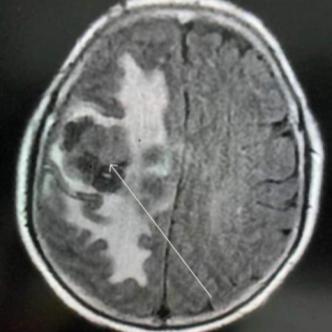

6月19日,汤女士因肢体乏力、口齿不清来到我院神经内科就诊,完善头部MRI检查后,发现其右额颞叶占位性病变,病情复杂。神经内科立即组织医学影像科、神经外科、血液肿瘤科、病理科等科室开展多学科讨论(MDT),经过深入研判和进一步检查,汤女士被诊断为原发中枢弥漫大B细胞淋巴瘤。为进一步治疗,汤女士被转入血液肿瘤科。

经过医疗团队的通力合作,汤女士肢体偏瘫、言语不清等症状均已消失。复查头部磁共振,显示肿瘤明显缩小。目前,汤女士不仅生活能完全自理,还能完成简单的家务劳动,生活重回正轨。